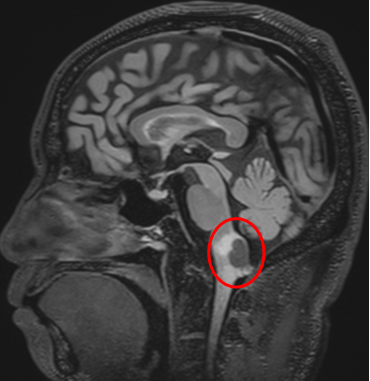

“病灶位于脑干,这不是普通的脑部手术。”拥有30多年脑干手术经验的巴特朗菲教授详细评估道,“如果用1到10分来评估手术难度,这台手术大概在5到6分左右。”面对着这个常常被成为“手术禁区”的延髓位置,巴教授显得从容不迫:“有些神经外科医生可能会认为这类手术无法进行,或者风险极高。但我一直在做这类手术。”巴教授不仅详细解析了手术入路选择、手术操作要点,还就术中神经监测、术后康复管理等关键环节进行了解答。

和巴教授同为德国人的Z先生,长期在中国生活。当不幸查出“延髓背侧占位”,虽然已经咨询过多个国家的神经外科医生,巴教授的回复让Z先生对于手术充满信心,最终选择在亚洲神经外科临床、科研、教学基地——北京天坛医院接受巴教授主刀的手术。